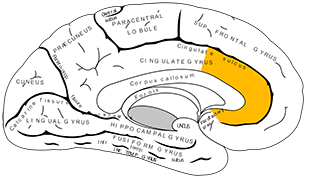

脳の構造 大脳を4つの領域に分けるランドマーク

脳の構造 大脳を右脳と左脳に分ける脳の溝